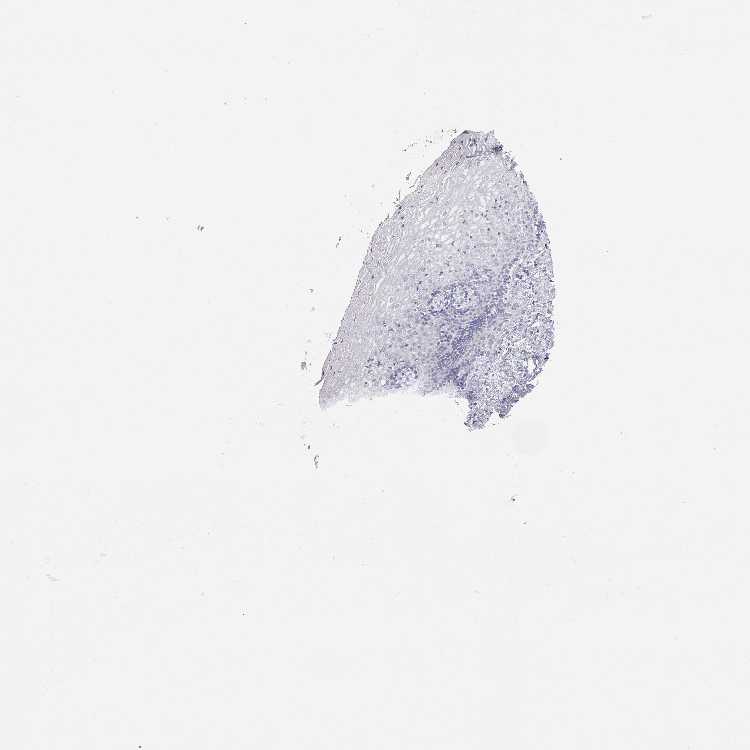

VAGINA - Antibody stainingi

Antibody staining in the annotated cell types in the current human tissue is reported as not detected, low, medium, or high, based on conventional immunohistochemistry profiling in selected tissues. This score is based on the combination of the staining intensity and fraction of stained cells.

Each image is clickable and will lead to virtual microscopy that enables deeper exploration of all samples and also displays staining intensity scores, fraction scores and subcellular localization as well as patient and tissue information for each sample.

Antibody HPA007042Antibody HPA030048Antibody CAB022682

Squamous epithelial cells Not detectedNot detectedNot detected